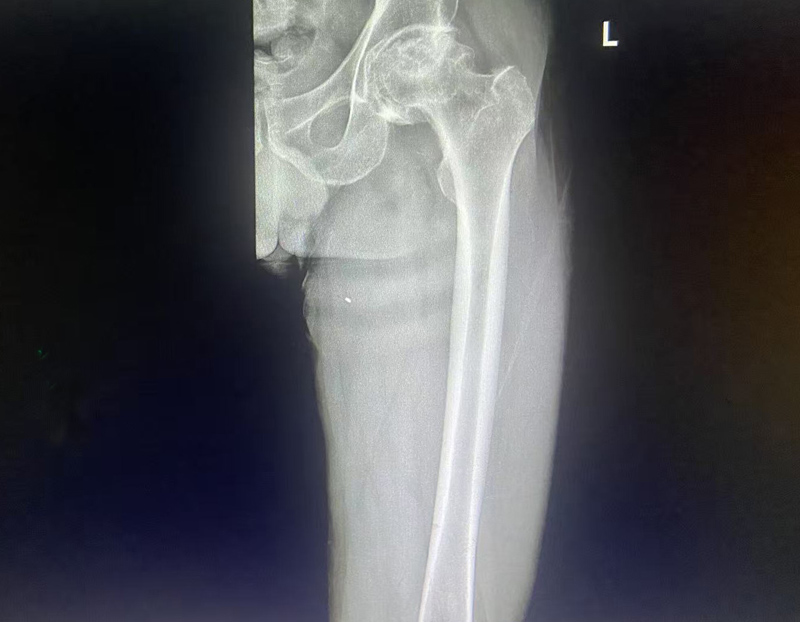

2025-11-14近日,骨科在麻醉科的协助下,成功完成我院首例左股骨头缺血性坏死全髋关节置换术。患者为中年男性,四年前出现双髋部疼痛,以左侧为著,行走约300米后疼痛即加重。曾在当地医院就诊,对症治疗效果不佳,于11月3日来到我院就诊并接受治疗。

在排除手术禁忌症后,于11月7日李李连亭主任亲自为患者施行左侧全髋关节置换术。整个手术过程顺利,术中出血量少,患者术后恢复迅速。